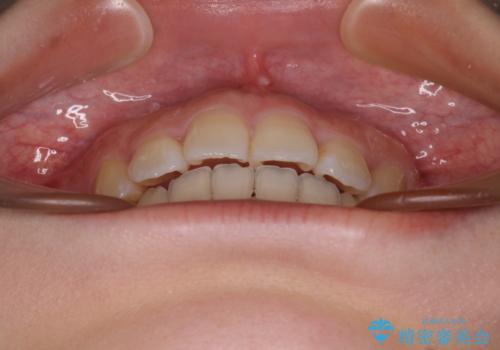

4本の歯を抜歯したことで、飛び出していた口元が引っ込み、横顔の印象が大きく改善されました。